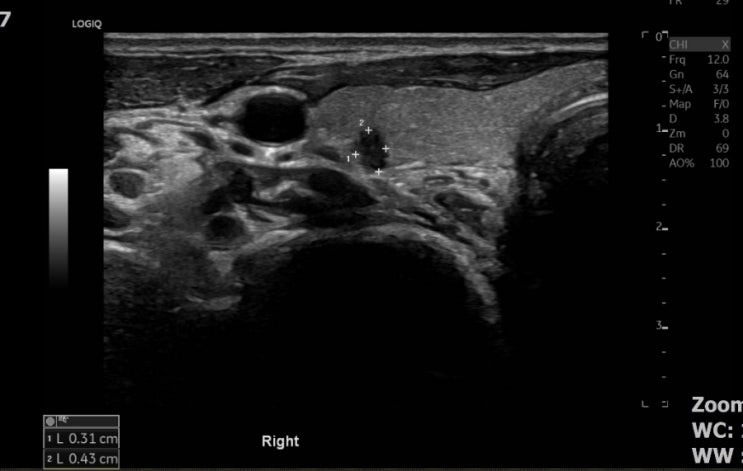

갑상선암은 예후가 좋은 암입니다. 새롭게 한건 진단되어 수술 예정입니다. 정기적인 초음파 검사로 건강을...

갑상선암

4mm 크기의 저에코 갑상선 결절 좌우 폭보다 상하 길이가 긴모양 둘레 마진도 미끈하지 않고 불균질합니다....